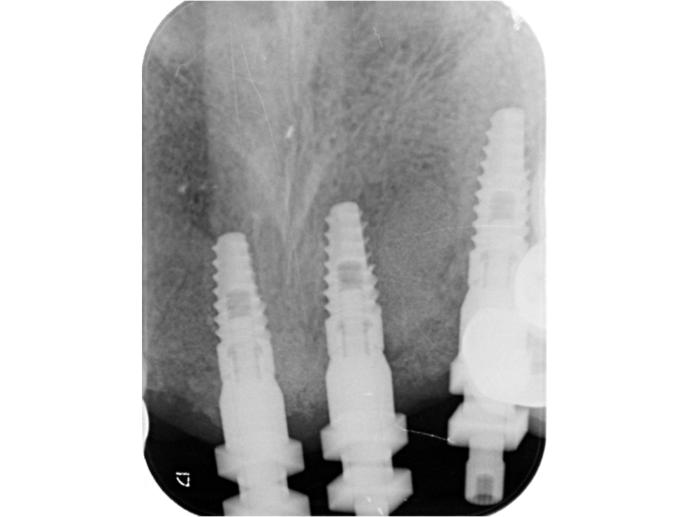

術中  斷牙即拔即種,共植入三顆